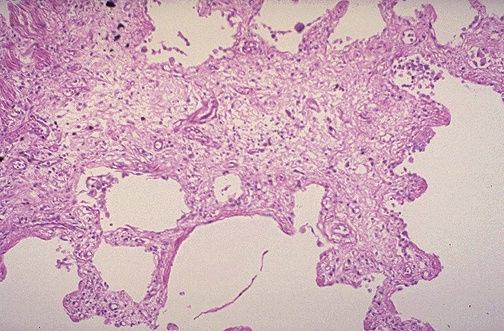

Карнификация Легкого: Микропрепараты и Диагностика

Раздел: Калейдоскоп образов